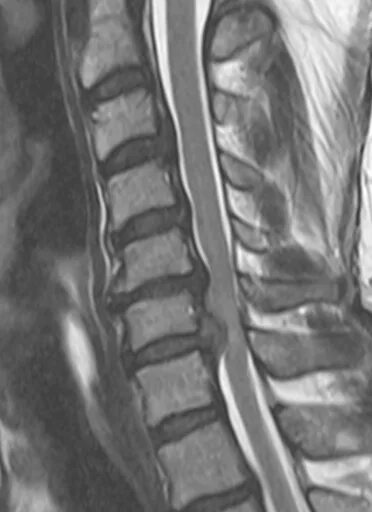

Грыжи дисков с3 с7